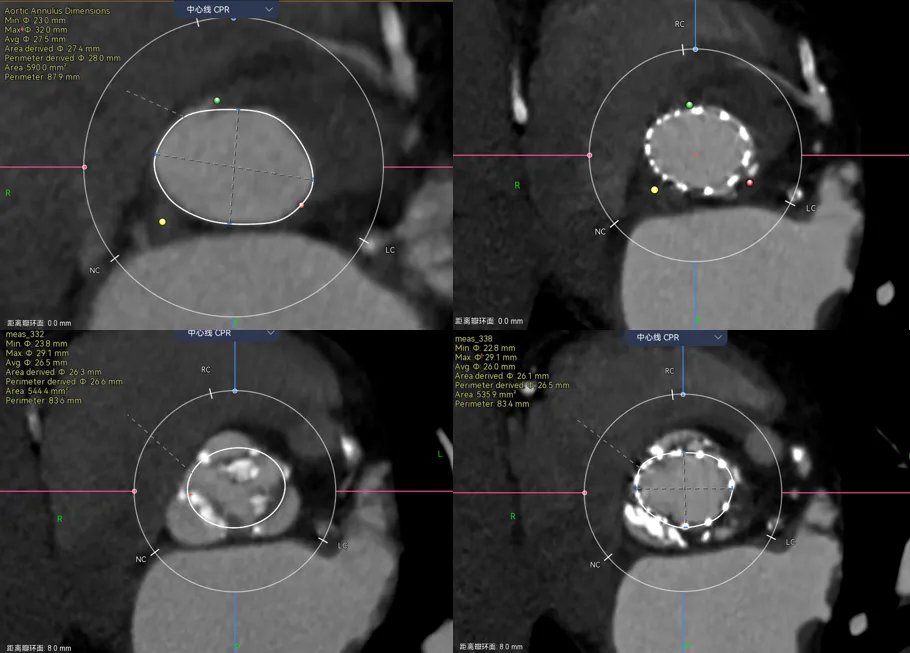

再来看一例三叶瓣的重度钙化对瓣膜的推挤,病例-4

遇见这种三叶瓣,边缘都有很重钙化的你会怎么画呢?瓣叶能推开么?要不要把边缘占满?这里考验的就是对钙化程度的综合理解了。刚刚也说了,瓣叶中间的钙化一般是可以推动的,除非连上了基底部有一大块的。而边缘的钙化,瓣膜往往没法占满。这就是钙化导致的瓣周漏的原因。

让我们来看看术前和术后预测的对比,预留的交界区域完全正确,瓣膜无法填满三个瓣叶的交界边缘,从瓣环到瓣上12mm都留有一丝缝隙,这类病例除非充分后扩贴一贴,不然多少都会有一点儿漏,术前可以充分预估到。